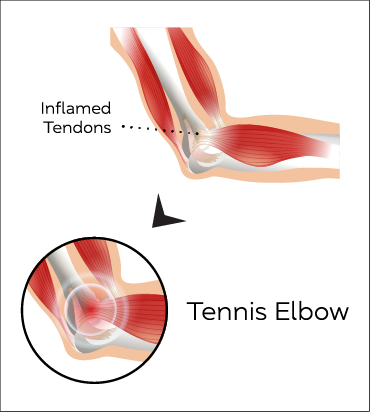

Tennis elbow

When tendons in the elbow are overloaded and repeatedly used, a person can develop a Tennis Elbow.

Tennis Elbow is common in people who have jobs that require repetitive motions of the arm and wrist.

Tennis elbow symptoms include pain and tenderness of the bone on the outside of the elbow. The pain may radiate into the upper or lower arm, with pain on hand movements like gripping, holding objects and turning door knobs.

Ultrasound can be used to identify and confirm the condition. An ultrasound guided injection using steroids, hyaluronic acid or regenerative medicine products can be offered as treatment.